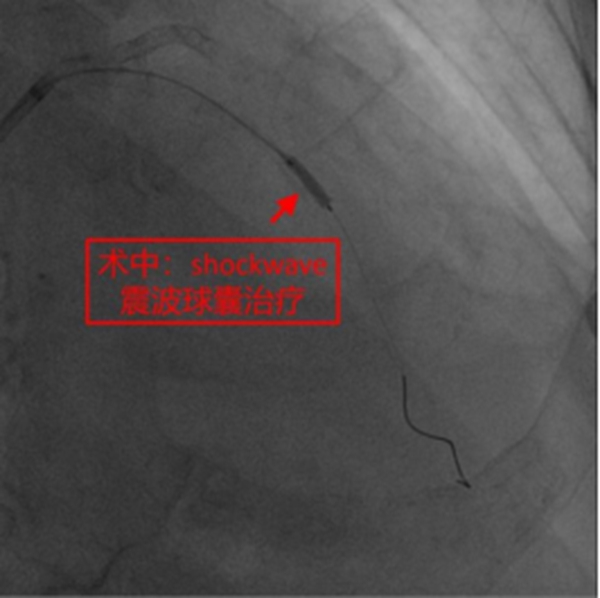

在征得患者及家屬同意,做好充分術前準備的情況下,冠脈介入團隊在冉擘力主任帶領下,按計劃給患者實施了血管內超聲(IVUS)指導下經皮冠脈旋磨+Shockwave沖擊波球囊碎裂鈣化斑塊及支架植入術,術中團隊克服了一系列困難,最終安全順利地完成了全部介入手術過程,完全碎裂了環狀鈣化斑塊,效果非常滿意,歷時約1個多小時,手術成功,病人安返病房。術后患者胸悶、氣短明顯緩解,對治療效果十分滿意。

而Shockwave沖擊波球囊則是將鈣化斷裂術+低壓力血管成形術整合在同一帶有脈沖電極的球囊導管內,在球囊低壓擴張時向病變提供未聚焦、圓周和脈沖式的機械能以高效和安全地破壞淺表與深層鈣化,也是目前唯一對深層鈣化有治療作用的技術。沖擊波球囊血管內碎石術是冠狀動脈斑塊旋磨術的重要補充,而且也為旋磨不成功的病變提供了新的選擇。臨床研究表明,沖擊波球囊治療重度冠脈鈣化病變手術成功率高、主要不良心血管事件發生率低、嚴重血管并發癥極少、管腔殘留狹窄率低、支架擴張良好。